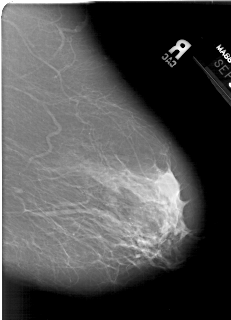

A_1386_1.RIGHT_MLO

RIGHT_MLO LINES 5746 PIXELS_PER_LINE 4156 BITS_PER_PIXEL 12 RESOLUTION 43.5 NON_OVERLAY